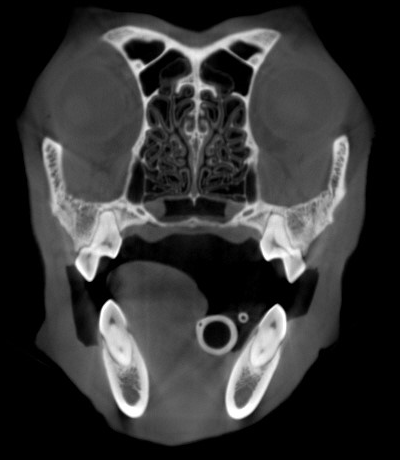

CT of a dog’s head in a similar position (different patient) without motion artefact – you can see how much crisper the image is. Note how much clearer the teeth appear.